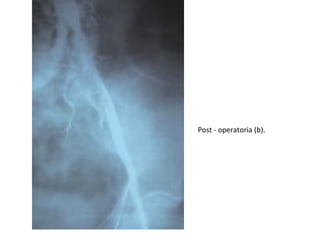

Post - operatoria (b).